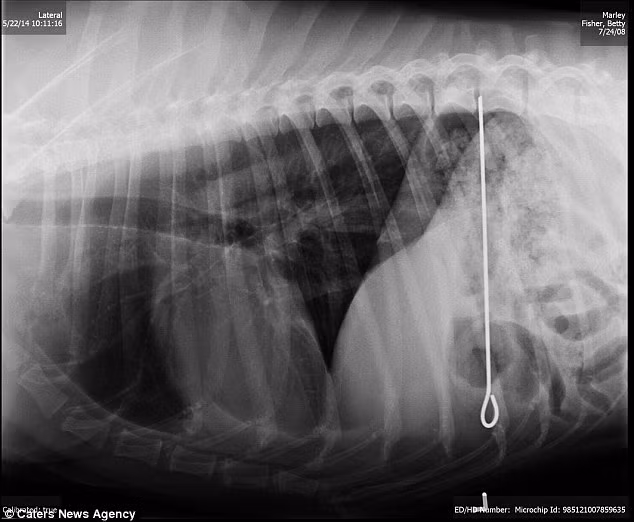

Chú chó có tên là Yoda đã nuốt cả thanh gỗ dài vào bụng.

Thanh gỗ dài gần bằng chiều dài cơ thể của nó.